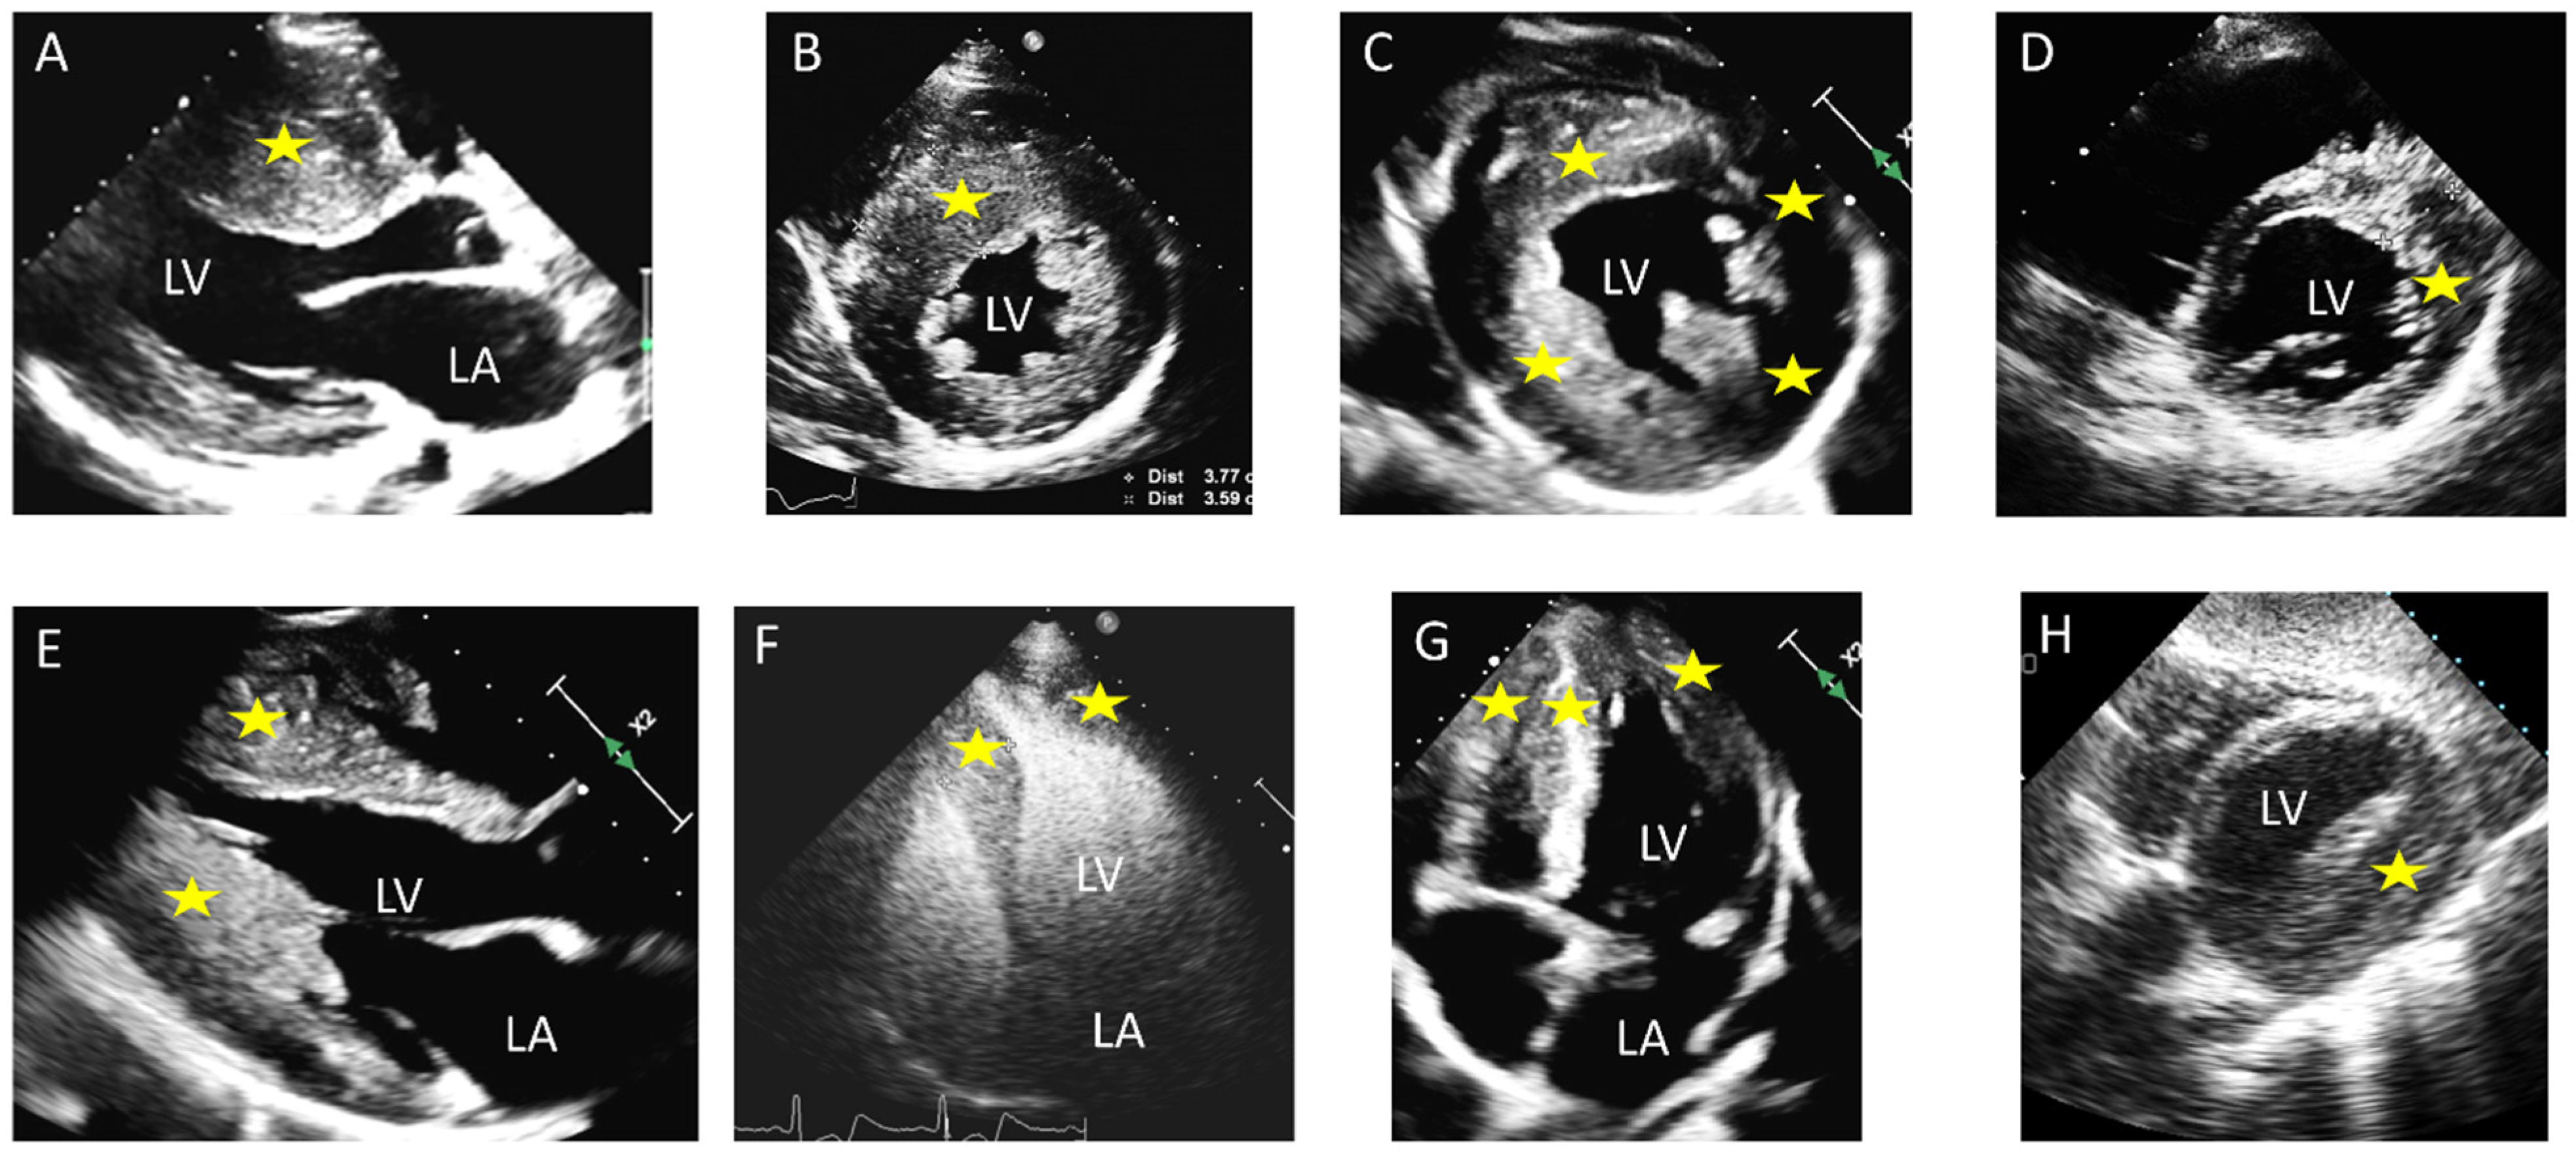

5. Mitral Valve Anomalies